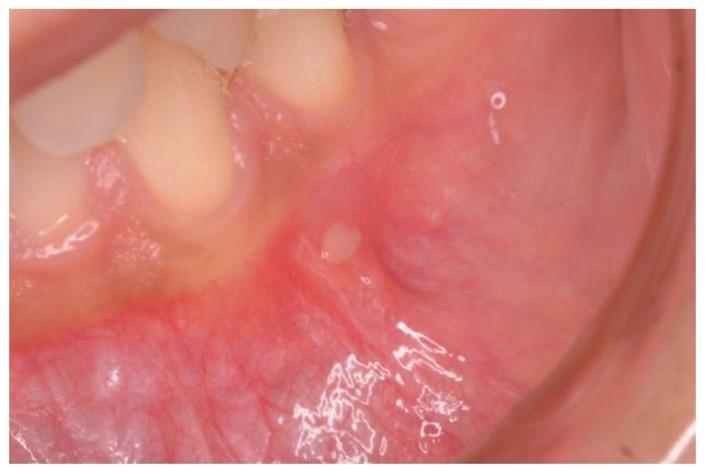

(1) Background: Celiac disease (CD) patients can be affected by mouth and tooth disorders, which are influenced by their gluten-free diet. The aim of our research was to evaluate the pathological conditions of the stomatognathic system observed in celiac patients on a gluten-free diet. (2) Methods: we consecutively recruited celiac patients on a gluten-free diet at our celiac center, as well as healthy volunteers. Two dentists examined all patients/controls and checked them for any mouth disorder. (3) Results: Forty-nine patients affected by celiac disease (age at test 31.8 ± 11.58, time on GFD 8.73 ± 7.7) and 51 healthy volunteers (age at test 30.5 ± 8.7) were included. Recurrent aphthous stomatitis was reported in 26 patients (53.0%) and in 13 (25.5%) controls ( = 0.005). Dental enamel disorders were reported in 7 patients (14.3%) and in 0 controls ( = 0.002), with none having geographic tongue. We found non-specific tooth wear, characterized by loss of the mineralized tissue of the teeth, in 9 patients (18.3%) and in 3 (5.9%) controls ( = 0.05). (4) Conclusion: Recurrent aphthous stomatitis and enamel hypoplasia are "risk indicators" that may suggest that an individual has CD. We detected a high prevalence of non-specific tooth wear that can be caused by several factors such as malocclusion, sleep bruxism, parafunctional activity, and age.

(1) 背景:乳糜泻(CD)患者可能受到口腔和牙齿疾病的影响,这些疾病受到他们无麸质饮食的影响。我们研究的目的是评估在无麸质饮食下乳糜泻患者的口腔颌系统的病理状况。(2) 方法:我们连续招募了在我们的乳糜泻中心接受无麸质饮食的乳糜泻患者,以及健康志愿者。两名牙医检查了所有患者/对照者,并检查了他们的口腔疾病。(3) 结果:共有 49 名患有乳糜泻的患者(测试时的年龄为 31.8 ± 11.58 岁,接受无麸质饮食的时间为 8.73 ± 7.7 年)和 51 名健康志愿者(测试时的年龄为 30.5 ± 8.7 岁)被纳入研究。26 名患者(53.0%)和 13 名对照者(25.5%)报告有复发性口腔溃疡( = 0.005)。7 名患者(14.3%)和 0 名对照者(0%)报告有牙釉质发育不全( = 0.002),无人有地图舌。我们发现了非特异性的牙齿磨损,表现为牙齿的矿物质组织丧失,在 9 名患者(18.3%)和 3 名对照者(5.9%)中发现( = 0.05)。(4) 结论:复发性口腔溃疡和牙釉质发育不全是“风险指标”,可能表明个体患有 CD。我们发现非特异性牙齿磨损的患病率很高,这可能是由咬合不正、睡眠磨牙症、副功能活动和年龄等多种因素引起的。